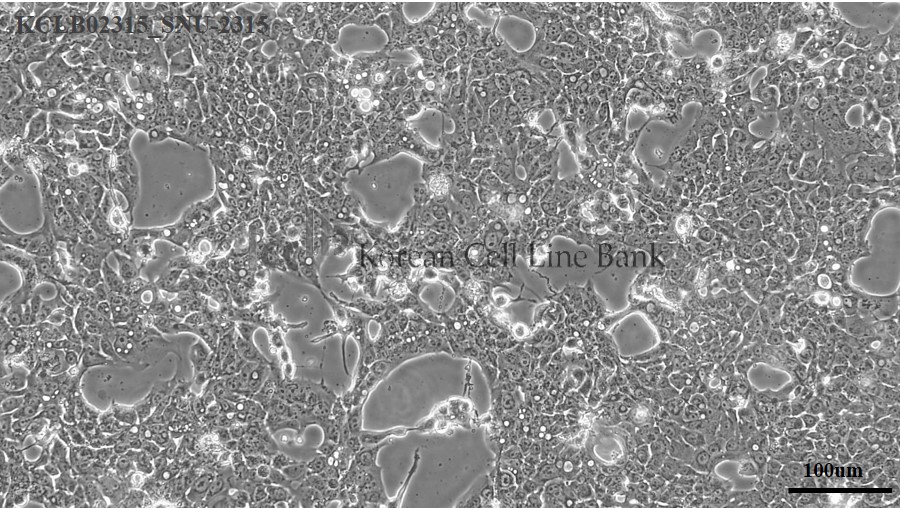

SNU-2315

| Origin |

| Cellular morphology |

epithelial

| Growth Pattern |

monolayer

| Histopathology |

adenocarcinoma